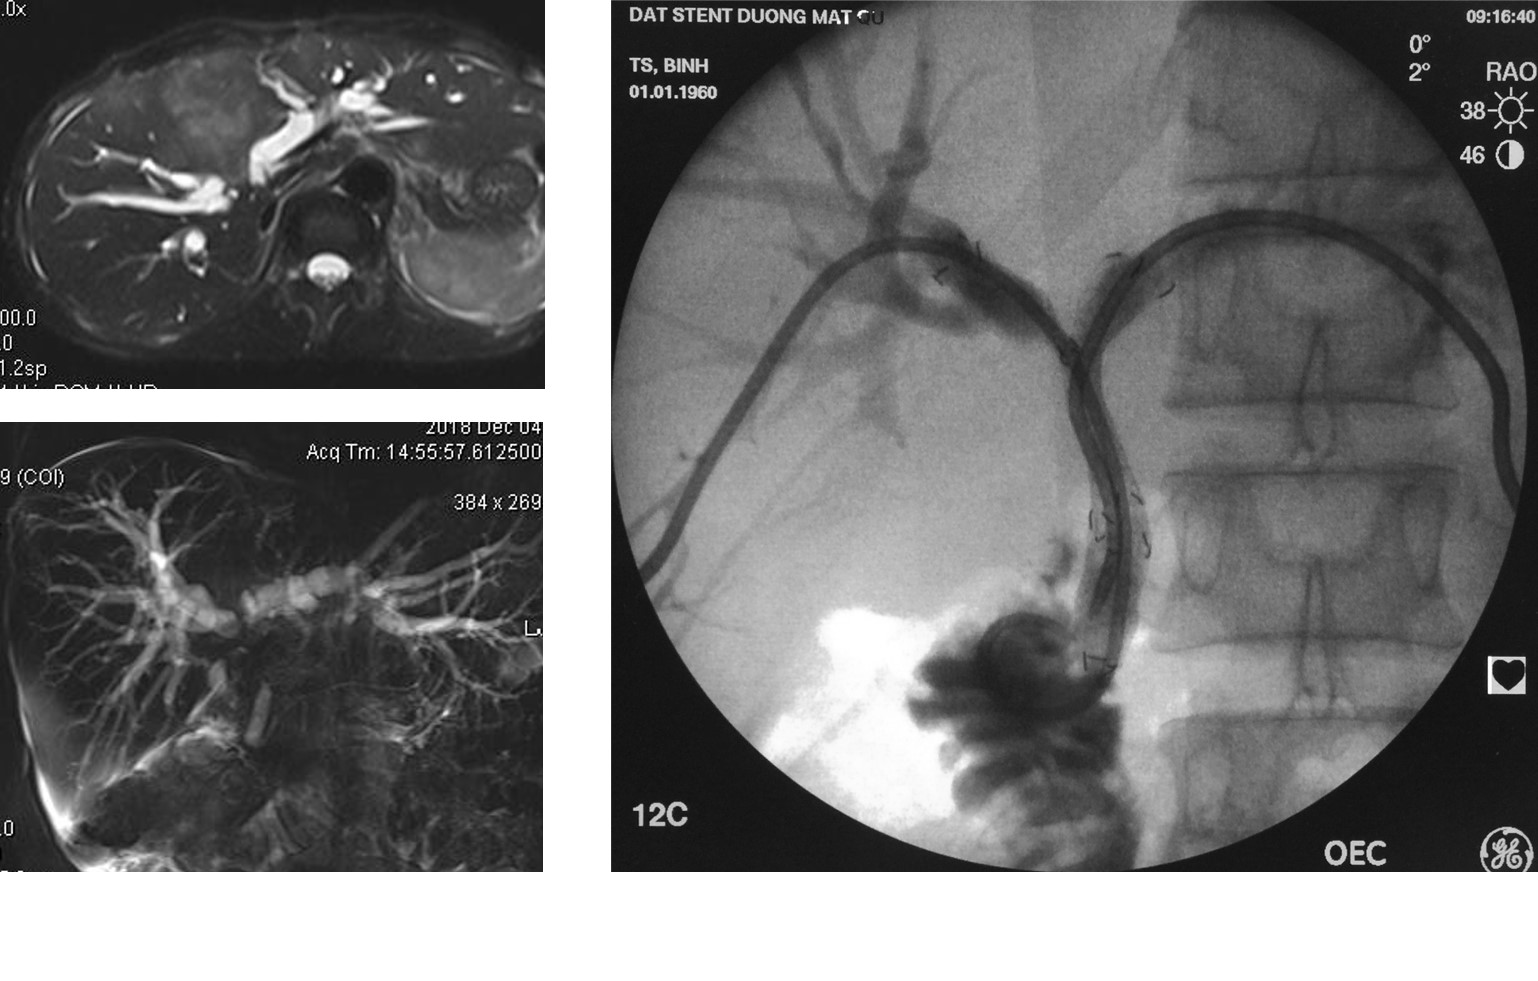

U đường mật rốn gan (Klatskin) xâm lấn hai bên. PTBD giảm áp và đặt stent đường mật qua da hai bên hình chữ Y (Y configuration) tái thông đường mật.